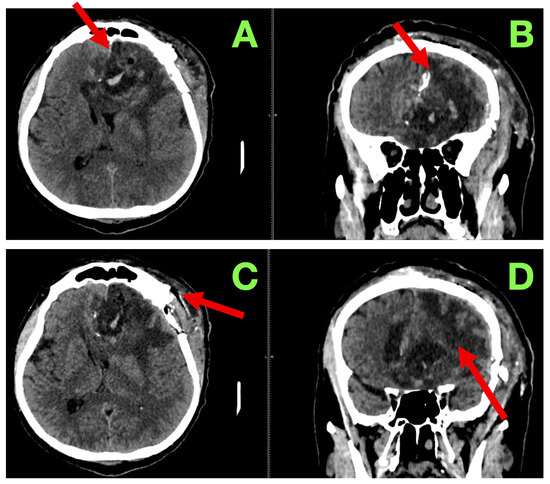

On examination, the strength of motor function was intact bilaterally with no noticeable asymmetries or fasciculations or evident fatigability in the exam. The deep tendon reflexes were symmetric and there were flexor responses on the Planta response testing. Gait and coordination were normal on testing. On language examination, the patient showed fluent expressive output with mild anomia, but observed accuracy with respect to syntax, repetition, and reading comprehension. On cognitive assessment there was intact short-term memory, attention span, and executive function testing. As part of standard follow-up, a non-contrast cranial CT (Figure 3) was completed at 3 months. This scan showed a stable post-operative cavity without any new enhancement in the cavity or hemorrhagic complication or indication of any new hydrocephalus. There was also considerable reduction in perilesional edema. The ventricular appearance had returned to their apparent normal appearance, with no evident midline shift/sub-dural collection/sub-acute delayed infarct. Relative to the original report, they interpreted the findings as consistent with radiological stability of the surgical site and that there continued no progression, particularly with the absence of any new findings.

Figure 3. Three-month post-operative cranial CT scan. (A): Axial section demonstrating a well-defined left frontal resection cavity (red arrow) with smooth margins and no residual mass effect. Compared to the immediate post-operative stage, most of the surrounding vasogenic edema has resolved. Ventricular configuration is symmetric, with no midline shift or hydrocephalus. (B): Coronal reconstruction confirming stability of the resection cavity (red arrow), with no evidence of recurrent mass lesion. Cortical–subcortical architecture around the margins remains preserved, and no abnormal extracerebral collections are present. (C): Caudal axial slice showing the inferior aspect of the resection cavity (red arrow), with basal ganglia and thalamic anatomy intact. No delayed ischemia, hemorrhage, or secondary injury is observed, and the overall appearance is consistent with post-operative stability at three months.